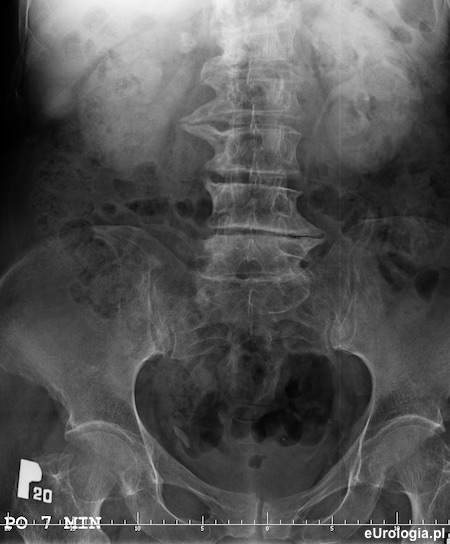

Zdjęcie urograficzne po 7 minutach - nefrogram po stronie prawej. Zakontrastowany UKM lewej nerki i lewy moczowód

Wodonerczowato poszerzony UKM prawej nerki i moczowód prawy aż do opisywanego cienia - złóg w dolnym odcinku prawego moczowodu